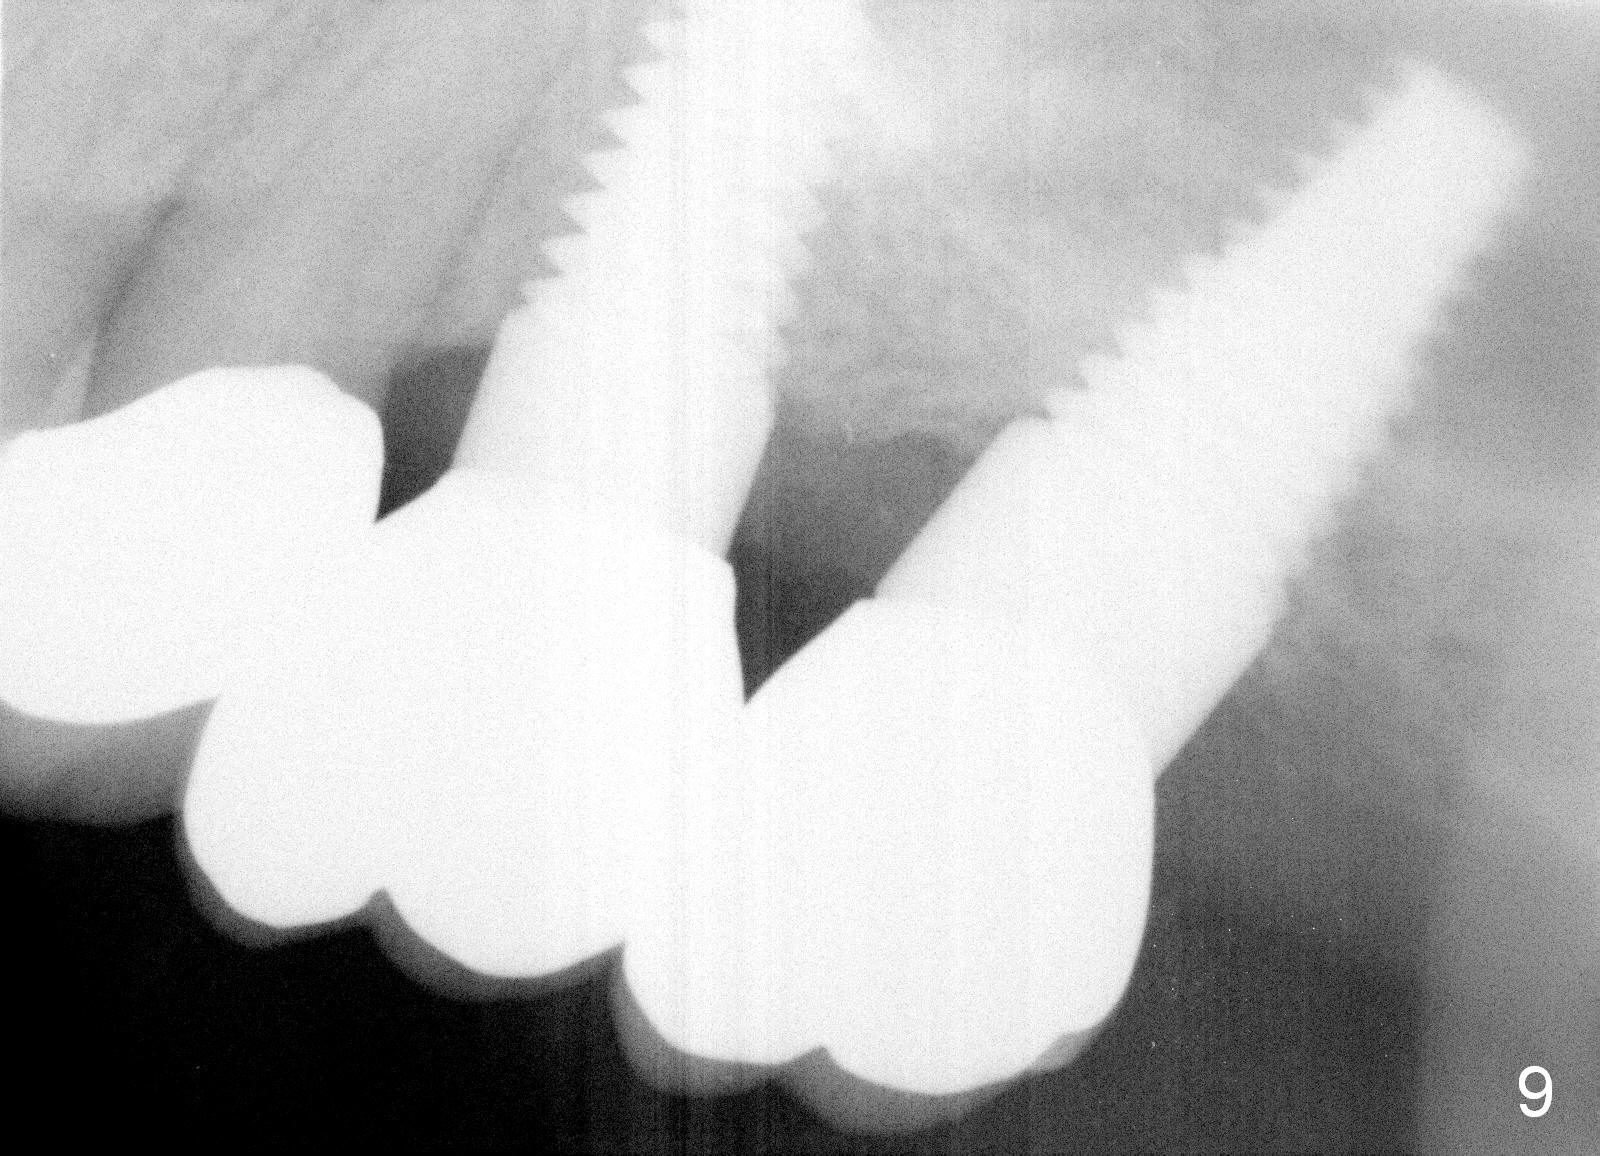

A 58-year-old man used to have a upper left 3-unit bridge. Two months after extraction and immediate implant at the site of the posterior abutment, an implant is planned to be placed at the site of the pontic, #14 (Fig.1). Osteotomy starts with a 1.6 mm pilot drill, followed by bone expanders, parallel to the crown of the tooth #13. The first intraop PA shows that 3.0 mm bone expander is close to the root of the neighboring tooth (Fig.2). No matter what is done to change the trajectory of the osteotomy using expanders according to the crown morphology of the neighboring tooth, the next 3 expander does not improve in parallelism (Fig.3). When a 6x17 mm tap is inserted (Fig.4 T), it is realized that axis of the tap is parallel to the axis of the crown of the neighboring tooth (black line), but not that of the root (red line). It is too late to change the trajectory drastically; a 6x17 mm implant is placed with insertion torque > 60 Ncm (Fig.5). It is best to change the trajectory as early as possible, e.g., after taking the first intraop PA and withdrawing the expander (Fig.6 black area) and as much as possible (red line; starting new osteotomy). It is quite similar to immediate implant. There is no bone loss 2 months postop (Fig.7), 18 months (Fig.8,9) or 34 months (Fig.10)post cementation, in spite of open contact between the crowns (Fig.10 black arrowhead). This is partially due to supragingival margin (Fig.11,12 (immediately pre-cementation)). No bone loss is noted 3 years 5 months post cementation (Fig.13).